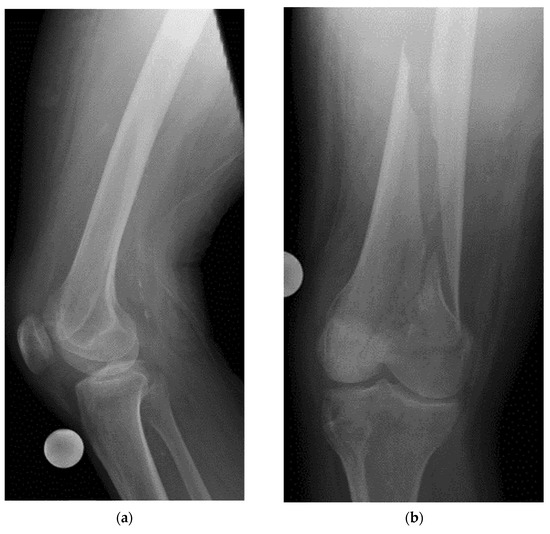

- Example: Stress Fracture

8.2. Screening of Patients with Suspicion of Occult and Stress Fractures (Figure 11 and Figure 12)

- Recommendation 2: Given the promising but limited evidence, ultrasound should be considered a first-line imaging tool for suspected occult fractures, except in the pelvis and vertebral column.

- Recommendation 3: Ultrasound should be used as first-line imaging for suspected stress fractures, with follow-up X-ray if evidence of a stress fracture is identified. Exceptions include pelvic and vertebral column fractures.